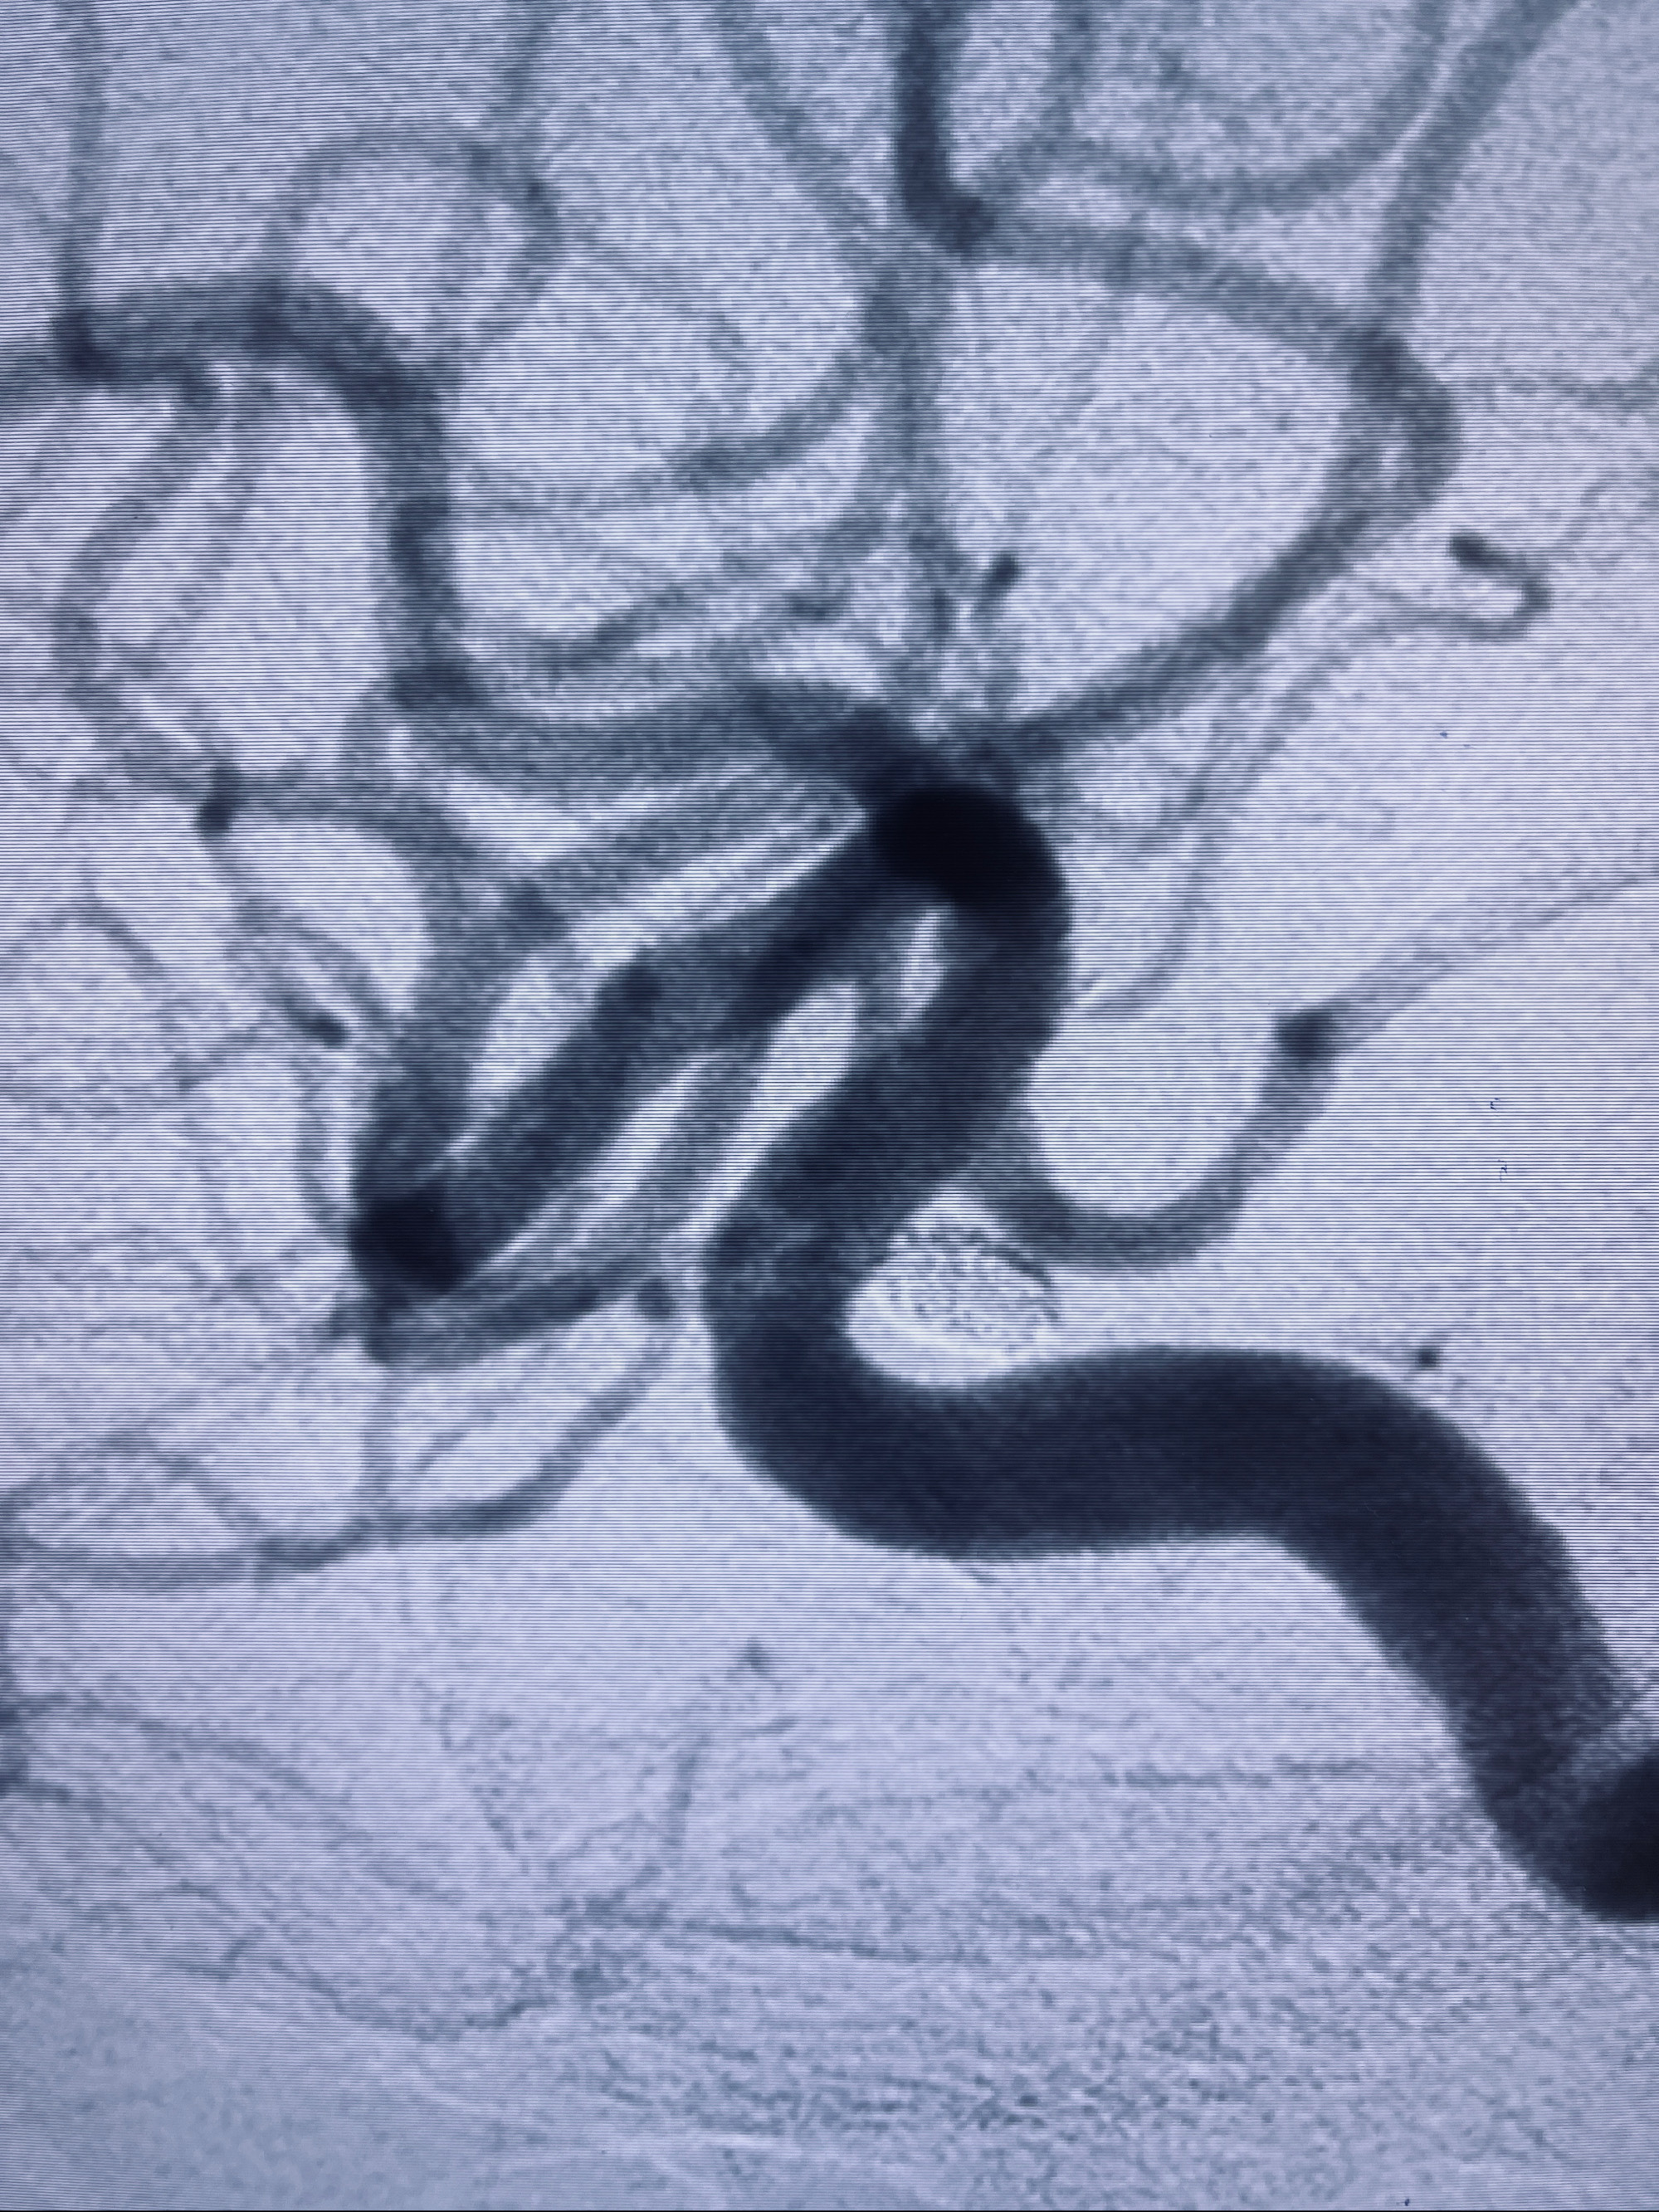

2022-09-29复查DSA